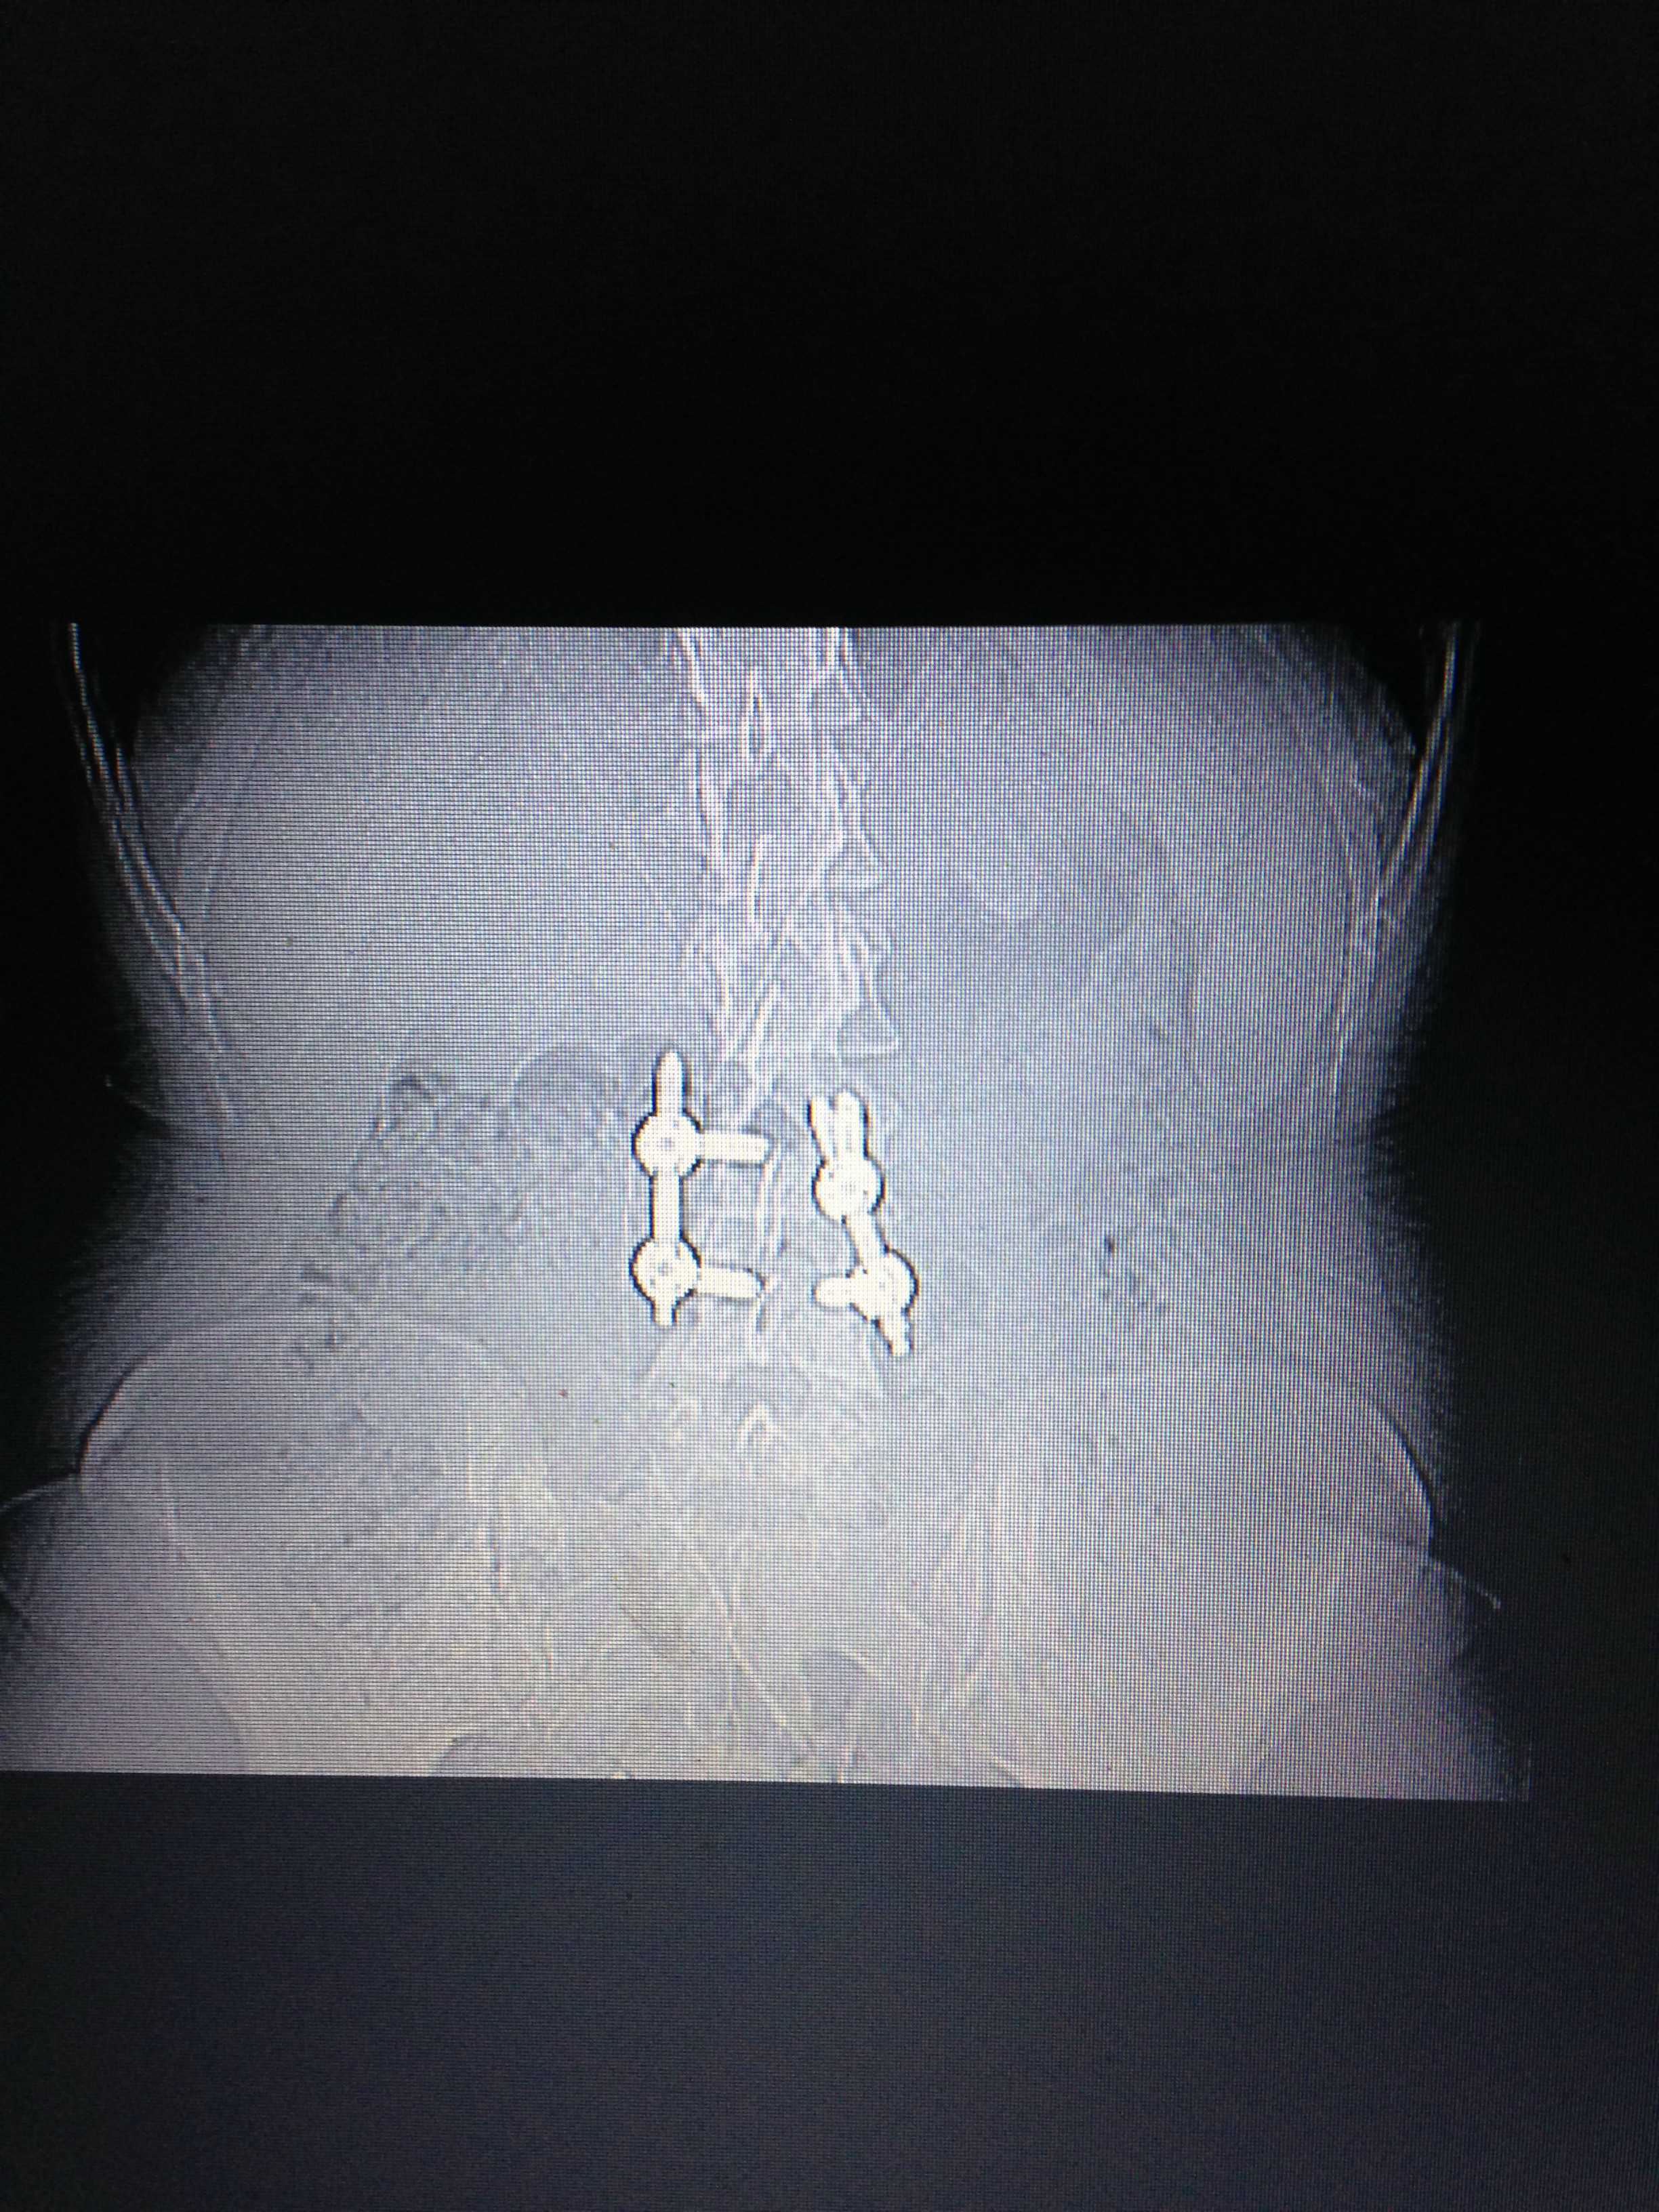

I demanded a CT scan and sure enough had two spinal breaks and the bone was swinging, so luckyily I did not become paralysed. They gave me a spinal fusion l3-4 with bone marrow, rods and screws. Six months later I learned how to walk again. I was gradually growing strong again, although I suffered left leg numbness post op, which never returned. I started Physio 10 months later and decided to travel as I felt I'd missed out.

My fiancé and I set off, but I had a fall in Calpe. I took myself to the hospital as my left foot went blue. That was April last year 2016 and I have slowly deteriorated since then. I told my surgeon I could still feel the bone moving in my spine, and he suggested to take the metal out. I demanded another scan, and it showed the fusion hadn't been successful, so taking the metal out wasn't an option.